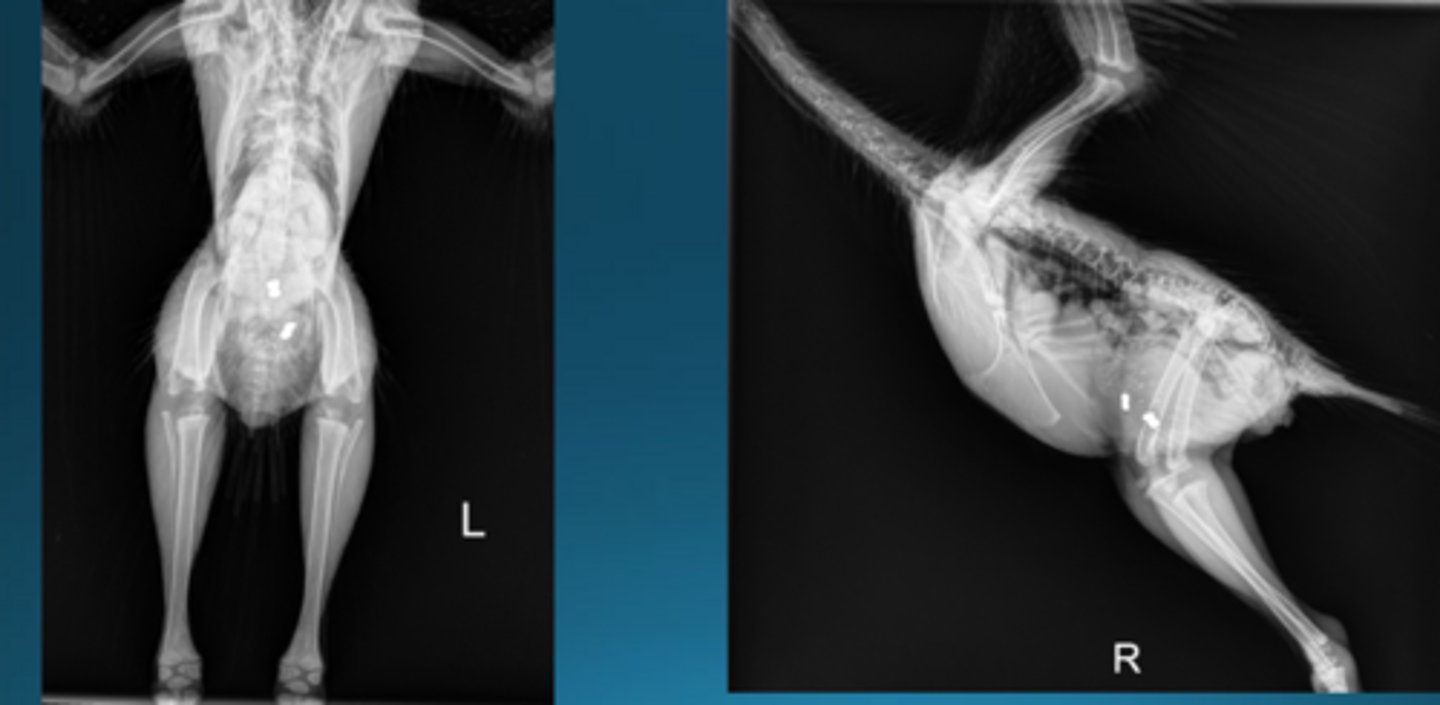

1. small egg

2. hernia = must do barium study to determine if repro. or digestive organs or inside

Describe some things you see in this bird

A 34 year old congo african grey has recently started having seizures at home. This is the radiograph. The bird has hypercholesterolemia. Tell me what you see and what you would do to treat

Metal opacities - lead pellets are a good differential for toxicity causing seizures in birds, zinc would be too

TREAT: CaEDTA to decontamination

A 4 month old peahen is presenting with seizures and you get this radiograph. What do you see and what can you do?